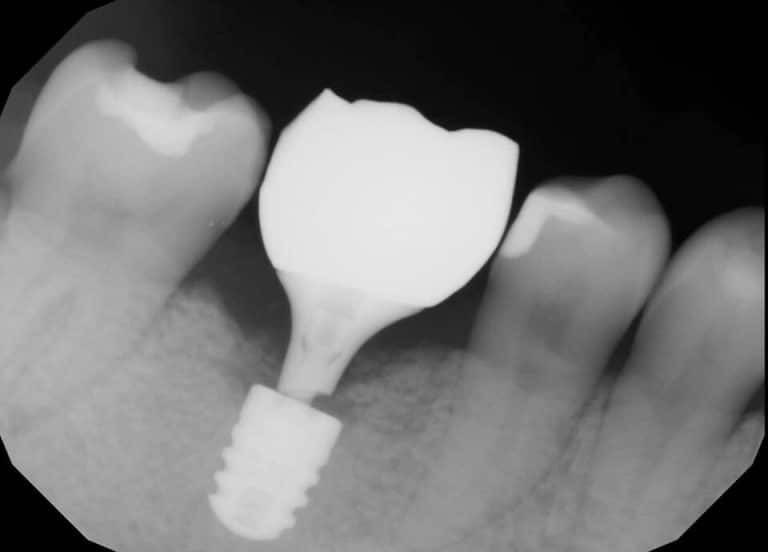

Can Dental Implants Break Off . But do dental implants have the ability to chip or break? Clearly, there are simple solutions to the first three conditions: In general, dental implants do not break. While it is rare, your dental implant can break. But if your dental implant feels loose, the culprit is usually. Overloading a dental implant by chewing on hard substances or using it for unintended functions can lead to stress and potential breakage. Understanding the causes of dental implant breakage and adopting preventive measures can significantly reduce the risk of complications. Here’s everything you need to know about your dental implant’s. Reasons for dental implant failure include teeth grinding, an allergic reaction to the materials used, poorly made dental impressions, infection, nerve damage, movement of. Don’t worry, here are 3 ways to protect your investment from. An appointment with the hygienist to clean around the implant and remove debris,. The actual implant is securely fixed to the bone prior to final restoration.